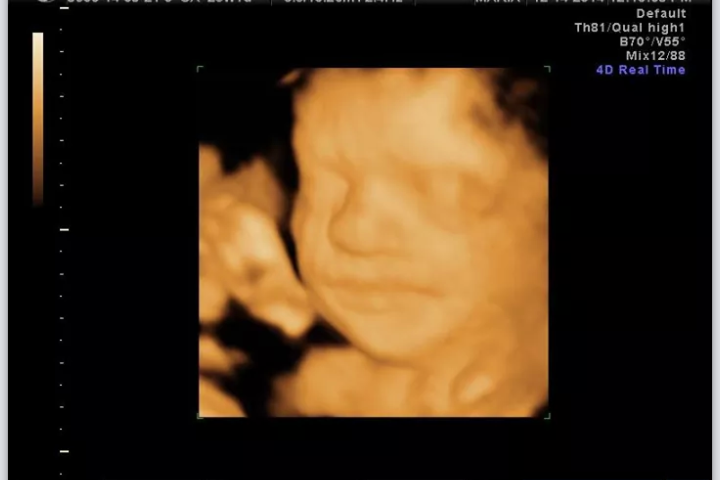

I couldnt sleep because im way too excited for my 3d u/s in a few hours. The more I stare at the 2d u/s where we got to see his lips, the more im like "he looks just like ME!" Haha, im hopeful.

AW: two of the shots from our elective 3d today! The technician said he had my nose and we were able to see the same little ridge in his chin that I have in mine! It took us awhile to see his mouth because he wouldnt stop sucking on his wrist and the umbilical cord. They said the second picture will probably be the best picture to do a newborn v. 3d u/s comparison. I cant wait!